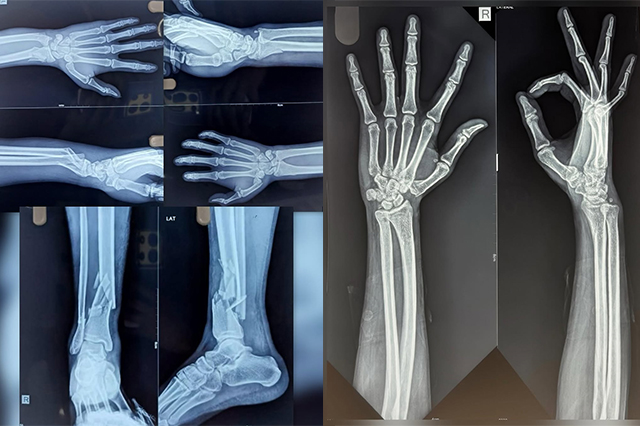

5 months ago, life changed for this young boy in an instant. A terrible accident left him with mu...

From Fracture to Full Function: A Story of Determination

-27yr/M who came to us with a complex elbow fracture after a severe fall. The elbow, one of the m...